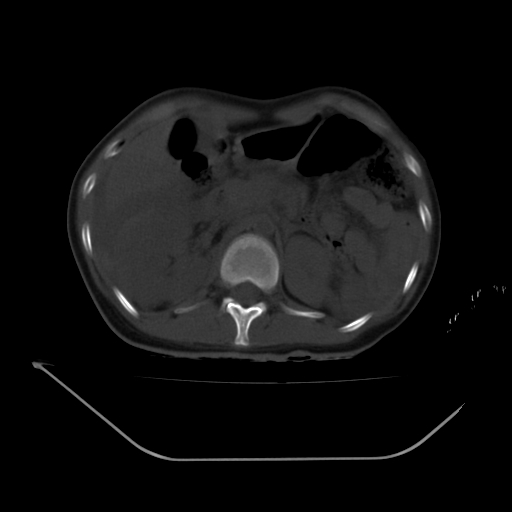

以下是引用liuyue在2008-7-19 13:02:00的发言:[br]1.肝右叶后下段及右肾挫裂伤伴腹腔积血。[br]2.右侧多发性肋骨骨折、横突骨折、右髂骨骨折伴周围软组织挫伤。[br]3.右侧腰大肌肿胀,并可见低密度影,如为气体,则肠道挫裂伤待除外。

以下是引用zhengfaming在2008-7-19 14:42:00的发言:[br]1.肝右叶后下段及右肾挫裂伤伴腹腔积血。脾脏挫裂伤待排[br]2.右侧多发性肋骨骨折、横突骨折、右髂骨骨折伴周围软组织挫伤。[br]3.右侧腰大肌肿胀,并可见低密度影,如为气体,则肠道挫裂伤待除外